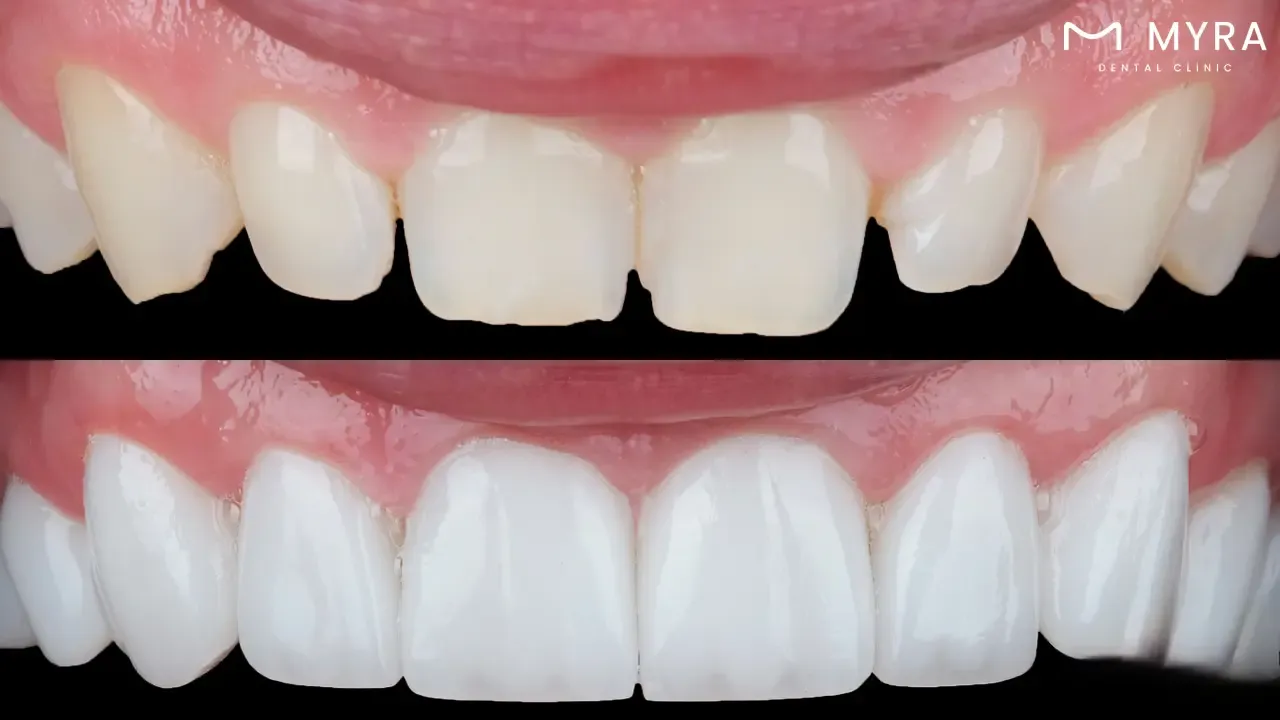

1.Porcelain veneering

Many cosmetic problems, including stains, discolouration, chipping, cracks, and uneven spacing between teeth, are fixed using the said treatment. They are a popular option for patients wishing to improve the appearance of their teeth because they are incredibly strong and long-lasting. These veneers are constructed specifically to fit over the teeth and are created to match the colour and shape of the neighbouring teeth, giving a smile a natural-looking and beautiful appearance. What is porcelain veneering? Porcelain veneering is a cosmetic dentistry surgery that covers the teeth' front surfaces with very thin porcelain shells to enhance their appearance.

A variety of cosmetic problems, like gaps between the teeth and discoloured, chipped, or irregularly shaped teeth are fixed with porcelain veneers. Two appointments are usually required for the treatment, during which the dentist prepares the teeth by removing a little bit of enamel, taking imprints of the teeth, and applying temporary veneers while the permanent ones are being made.

The dentist removes the temporary veneers after the permanent ones are prepared and use special dental cement to attach the permanent veneers to the teeth. Porcelain veneers are strong and long-lasting, and with the right upkeep and care, they provide patients with an attractive and realistic-looking smile for many years.

The durability and lasting effects of porcelain veneers are a benefit. Porcelain veneers are made of sturdy, high-quality materials that resist daily use's typical wear and tear. Porcelain veneers are an extended investment in a patient's oral health and aesthetics because they last up to 15 years or more with proper care. Furthermore, porcelain veneers are non-invasive and only slightly alter the native tooth structure, overall stronger and healthier teeth result. Overall, porcelain veneers provide a secure and efficient means of obtaining a lovely, healthy smile that endures for years. Porcelain veneering is a common and efficient cosmetic dentistry technique that assists patients in achieving a more attractive and self-assured smile. They talk to a good cosmetic dentist to find out if porcelain veneers are the right choice for their needs and goals.